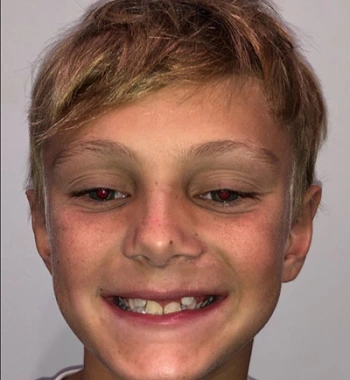

Actual Patient: Alexander

After

Severe “Underbite”, Narrow Jaws, Adult Teeth Not Growing In

Front View